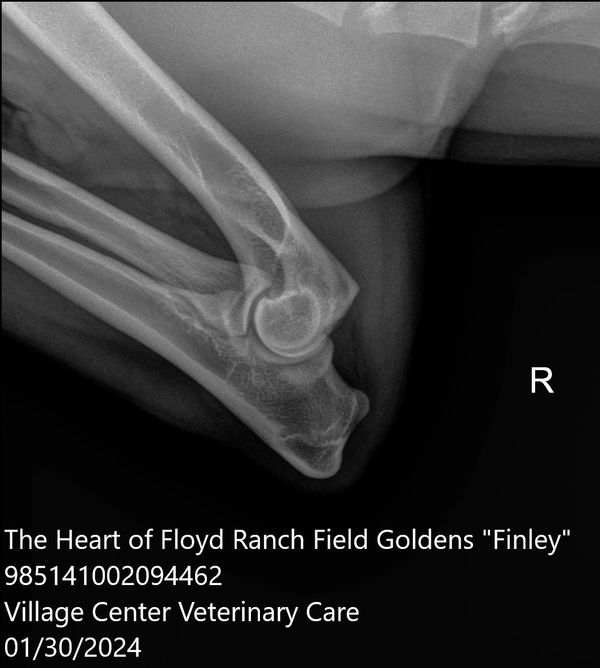

Finley has "normal" elbows, this is a radiograph of her Right Elbow